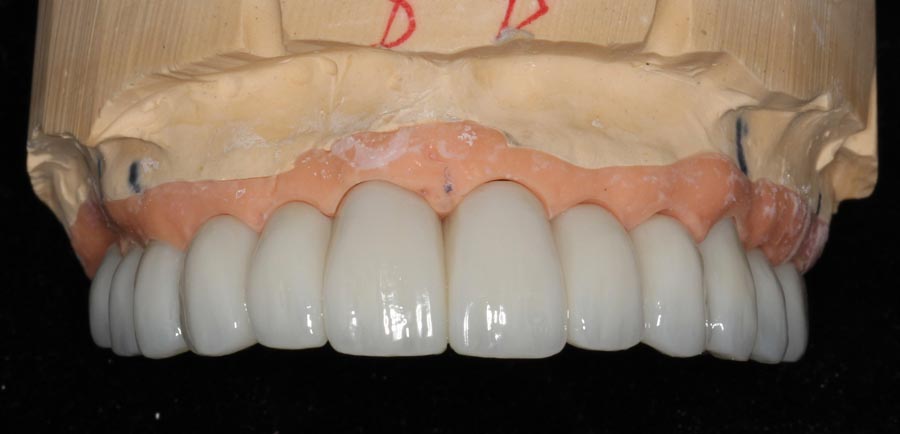

Smile GalleryImplant RestorationsFull Mouth Implant Restoration Full arch zirconia implant bridge (full smile) 1 of 37 Pre-op full smile Pre-op lips retracted Pre-op panoramic x-ray Extraction of strategic teeth Placement of implants Extraction of some remaining teeth after verification of adequate implant stability Occlusal view Post-op panoramic x-ray Immediately fabricated provisional restoration (tissue side view) Immediately fabricated provisional restoration (occlusal side view) Immediate provisional delivered on day of surgery Immediate provisional 2 weeks later Scalloped tissue developed from the provisional at 2 weeks Jig used for making a master impression Provisional in place (full smile) Provisional in place (lips retracted) Provisional in place (right side) Provisional in place (left side) Wax try-in (full smile) Wax try-in (right side full smile) Wax try-in (left side full smile) Wax try-in (full face, lips together) Wax try-in (full smile) Wax try-in (right side) Wax try-in (left side) Wax try-in (lips retracted) Full arch zirconia implant bridge on master cast (frontal view) Full arch zirconia implant bridge on master cast (occlusal view) Implant positions and soft tissue representation on master cast (occlusal view) Soft tissue representation on master cast (frontal view) Full arch zirconia implant bridge (tissue side view) Soft tissues on day of delivery (occlusal view) Soft tissues on day of delivery (frontal view) Full arch zirconia implant bridge delivered (lips retracted) Full arch zirconia implant bridge (lips retracted, close up) Post treatment panoramic x-ray Full arch zirconia implant bridge (full smile)